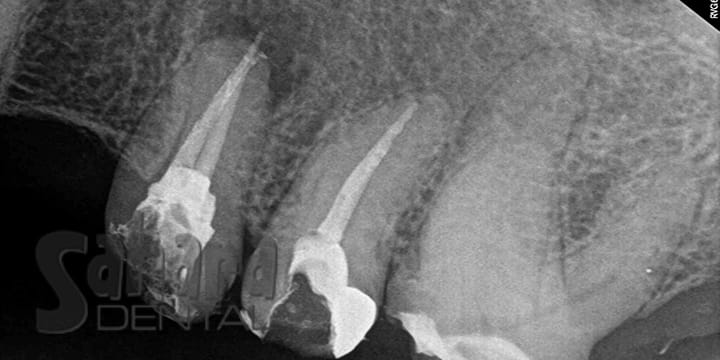

Successful Retreatment of Two Root Canals

Dr. Jamal expertly retreated two root canals in Fontana, CA, where the original treatments were too short and led to periapical lesions. By meticulously cleaning and sealing the canals, the infection is set to be eliminated, promoting healing of the surrounding tissues.